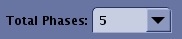

Table 1. Image legend Number Description of Detail tab 1 Total time excluding Mask. 2 Duration for Mask or non-wash-in phases. 3 Temporal resolution for wash-in phases. Table 2. Multi-Phase tab selections Selection Description Total Phases

- The Total Phases does not include the mask phase.

- For a prostate exam, enter the number of phases required to adequately capture the contrast wash-out, approximately 6 minutes.

- For a breast exam, enter the number of phases required to adequately capture the contrast wash-out, approximately 10 minutes.

Wash-in Phases

- The number of phases from the time of injection to the completion of contrast uptake in the area of interest.

- For a liver exam, enter the number of wash-in phases that will fit within a breath-hold